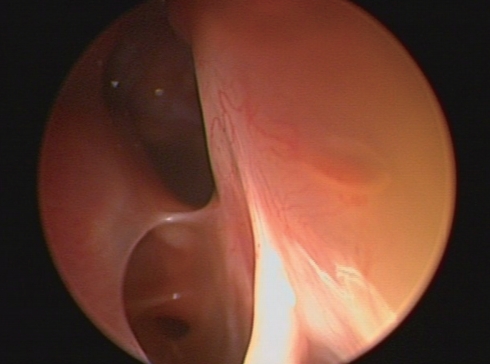

아래 내시경소견은 우측전두동에 풍선카테터 부비동확장술 시행 후 11개월 된 소견이다. 풍선카테터 부비동확장술에 대한 설명으로 맞는 것은?

① 전신마취하에서만 수술이 가능하다.

② 점액섬모기능을 보존하는 최소침습수술이다.

③ 심한 골염을 동반한 경우에도 사용할 수 있다.

④ 광범위한 용종이 있는 경우에도 사용할 수 있다.

⑤ 심각한 합병증의 발생빈도는 고식적 내시경 수술과 비슷하다.